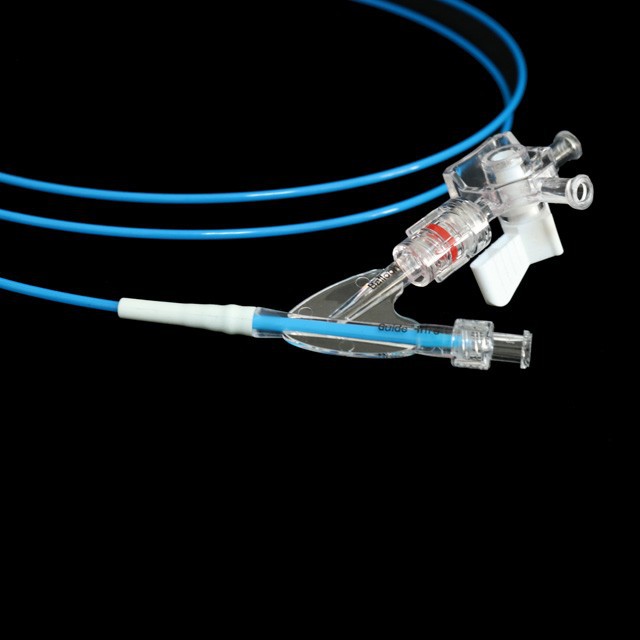

Pressight ከፍተኛ ግፊት መቋቋም እና ደህንነቱ በተጠበቀ ሁኔታ ላይ ከውጭ ከውጭ ለመግታት ከግምት ውስጥ ይግቡ

Mult ባለብዙ ክንፍ ከሚያስደስት በኋላ ቴርሜትሪክስ ደስ የሚሉ የመቋቋም ችሎታ እና ተለዋዋጭ ሽርሽር ከስራ ሰርጡ .}

The የቱቦው ምርጥ የቱቦው ተስማሚ ንድፍ ለስላሳ እና ጥሩ የመለጠጥ ችሎታ, ጠንካራ የመቋቋም ችሎታ እና ቀላል አለባበስ .

● የባለቤትነት በሁለቱም ጫፎች ላይ የሬዲዮአክሲክ አመልካቾች በ x-Ray {{1} ስር ትክክለኛ አቀማመጥ ሊያቀርቡ ይችላሉ

● ቅድመ-ግቤት 0 . 035 "ለስላሳ ጉርሻ እና ማርቆስ የግንባታውን ቅጥር ሽቦው ርዝመት ለመገመት ቀላል የሆነ.